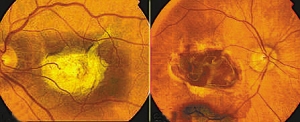

患有衰老性黄斑病变(左)和健康的眼睛(右)

干细胞是人体的“主细胞”,能够“转变”成其他细胞并充当人体的“维修工”。借助于维生素以及其他化学物质,兰萨将干细胞转化成健康的眼部细胞,再将其注射进患者眼部,“取代”因衰老性黄斑变性及其他致盲因素而发生病变的眼部细胞。这项实验此前已经在动物身上取得成功。

据悉,有望接受胚胎干细胞失明疗法的患者主要包括青少年以及患有遗传性失明症的年轻男女。到2011年,干细胞失明疗法有望在患有衰老性黄斑变性的老年患者身上进行实验,这种病是最为常见的一种失明症。